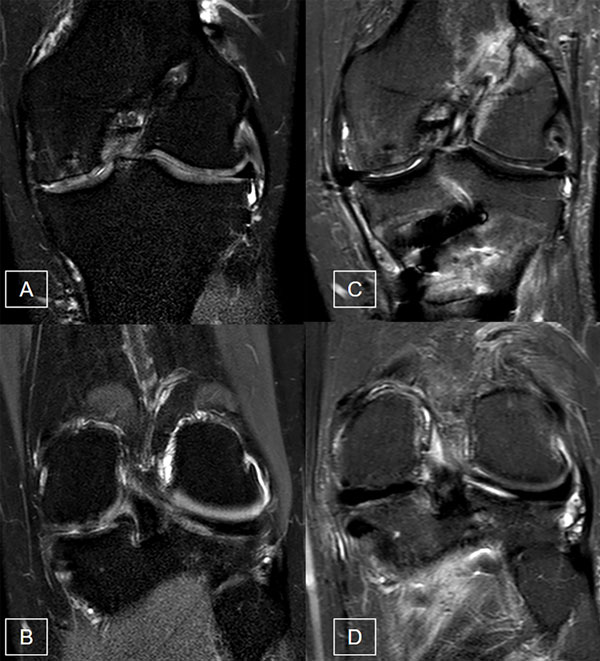

Se realizó RM en todos los pacientes para constatar la insuficiencia del compartimento medial secundario a la meniscectomía, así como la indemnidad del resto de las estructuras articulares con una adecuada estabilidad ligamentaria y superficie articular. Aquellos casos con lesiones ligamentarias o condrales concomitantes se trataron de manera simultánea en el mismo tiempo quirúrgico (fig. 3).

Figura 3: RM de rodilla pre y postoperatoria. A y B) Cortes coronales preoperatorios en STIR donde se evidencia la ausencia del menisco interno y las lesiones osteocondrales asociadas. C y D) Cortes coronales en STIR postoperatorios con el TAM en el compartimento interno.